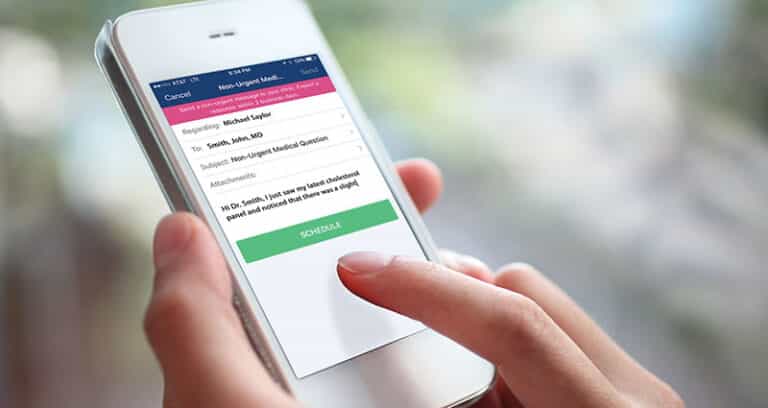

A Real Person’s Guide to Establishing Yourself With a Doctor

So, you know having a primary care provider (PCP) is important, but how do you actually get started? We’ve got you covered with a seamless process that makes establishing care a breeze. Step 1: Explore Your Options Head over to our online directory of providers, where you can browse profiles based on location, gender, language preferences…